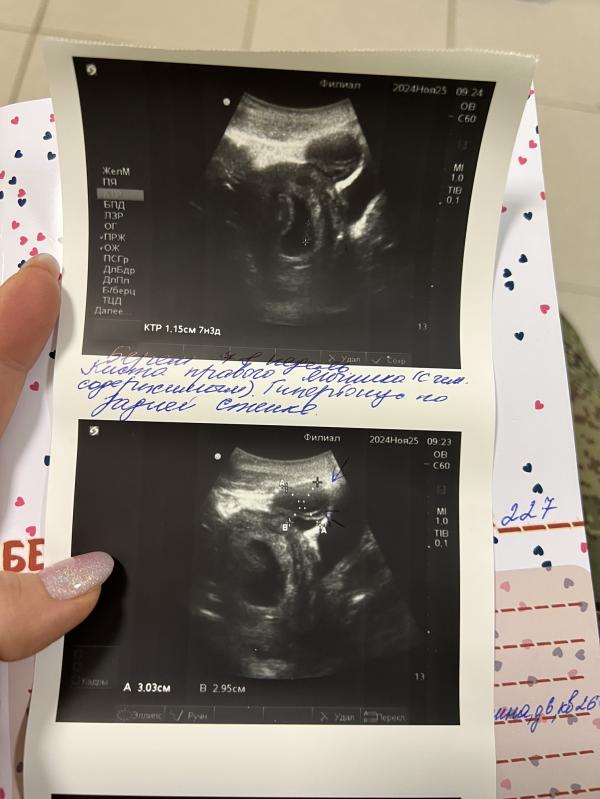

Очередное узи! (Четвертое уже🙈)

ЧСС 138, ктр 1,15 см,

Кисту еще увидела, вроде киста желтого тела.

И тонус по задней стенке. Половой и физический покой, и сажусь на дюфастон 🙈